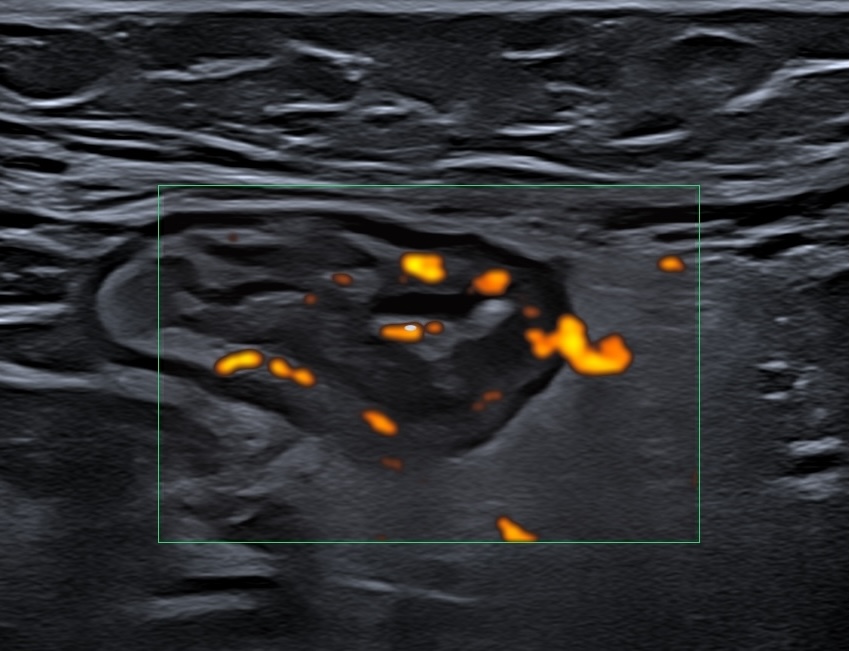

Mesure de l'activité des MICI

Utilisation de l'échographie pour mesurer de la réponse aux traitements par l'échographie